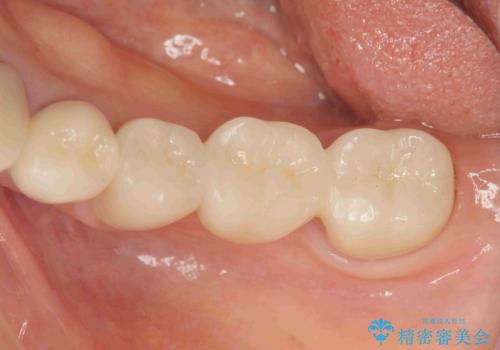

清掃しづらく、見た目の気になるブリッジ

- 毎回食事のたびに食べかすがつまり、見た目も気になる銀歯のブリッジやりかえを希望され来院されました。

精度の高いジルコニアブリッジの製作に加え歯茎にぴったりとそわせたオベイトポンティック形態とすることで清掃性・審美性に優れたブリッジを製作します。

歯ぐきの形態にそわせ、凸型でくぼみのないオベイト型のポンティックはプラークの溜まりにくく審美性も達成できるポンティック形態です。